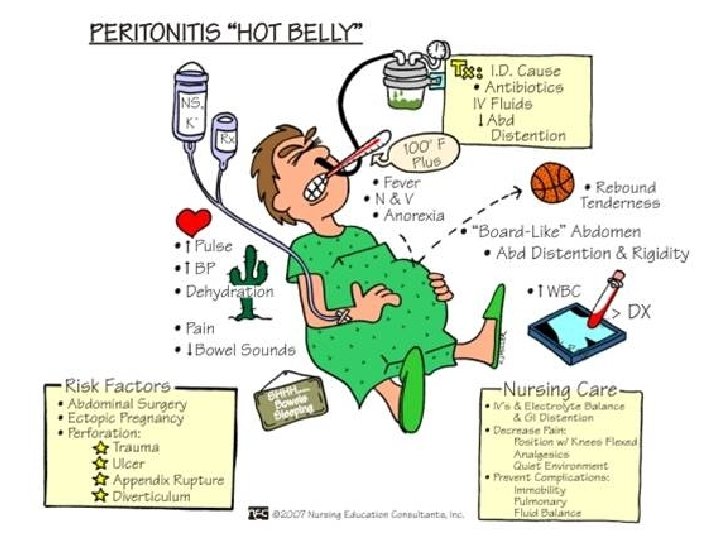

• - KOMPLIKACIONET: Appendix i gangrenizuar Perforim i appendix-it Peritonitis Abscess Sepsis

TRAJTIMI: - Hospitalizimi - Monitorimi i parametrave vital - Nuk lejohen analgjezik!!! (sepse maskojne kuadrin klinik) - Antibioterapi iv - Kirurgji: apendektomi e hapur/ laparaskopike